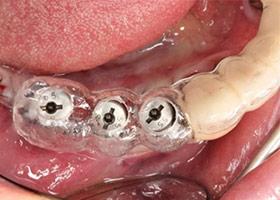

10.植入人工牙根於健康的齒槽骨。

11.配合手術導引板,精準植入理想位置。